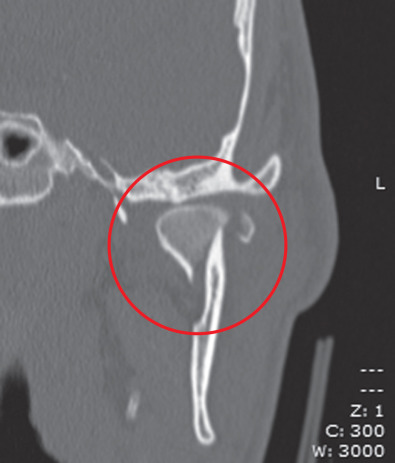

Fig. 1.15.9

CT of a diacapitular fracture. Note that the fracture line begins on the articular surface, goes through the head of the condyle and may extend outside the joint capsule on the medial side.